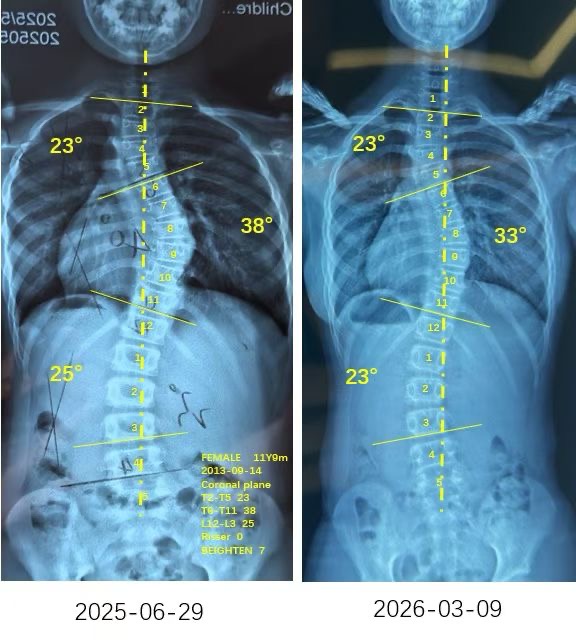

我是小玉,A1型胸弯38度降至33度,旋转13度降至4度,体态改善明显~

案例主人:小玉 发现侧弯年龄:12岁 侧弯情况:Cobb角度38度

直到现在我在衷德脊柱训练快半年了,最近拍片发现我的胸弯角度从38度降低到了33度,胸椎旋转也从13度降低到了4度,我和妈妈都很高兴。谢谢杨博士和衷德团队的所有人,我还会继续认真努力的矫正训练!

To date, I have been undergoing Zhongde Spinal Training for nearly six months. Recent x-ray revealed a reduction in my thoracic curvature angle from 38 degrees to 33 degrees, and thoracic vertebral rotation decreased from 13 degrees to 4 degrees. Both my mother and I are delighted. We extend our gratitude to Dr. Yang and the entire Zhongde team. I will continue to diligently pursue corrective training with unwavering commitment!